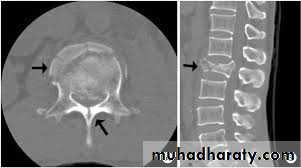

CT Scan :

Accurate assessment of bone.1- Comminution.2- Canal compromise.

Burst fractures

• 15 % of TL#s• Anterior&middle column failure.(Axial compression)

• Most common at T/L junction

• Neurological deficit incidence is higher.